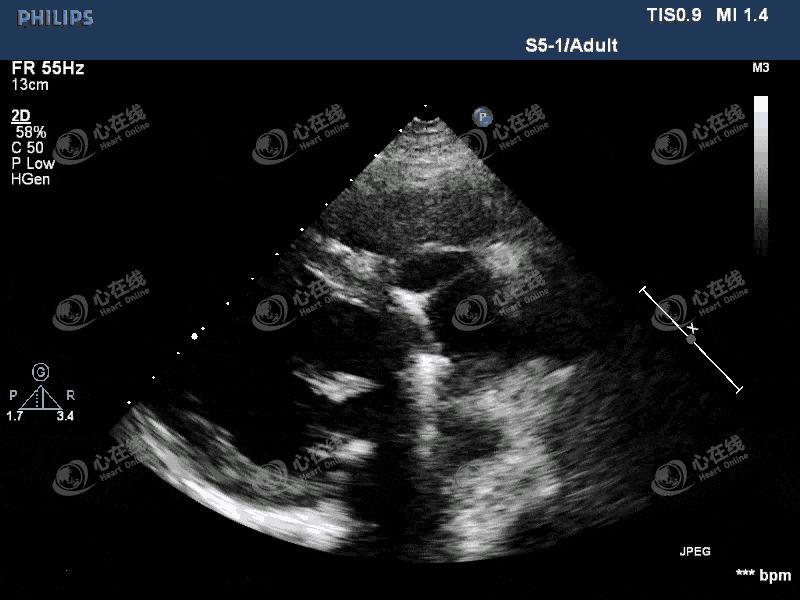

【超声心动图】

图1 左室长轴切面:左心饱满,主动脉瓣为人工机械瓣,缝合环活动度增大,主动脉根部前壁及后壁紧邻机械瓣处可见一隔膜样回声,其上可见破口,该处可见无回声区。